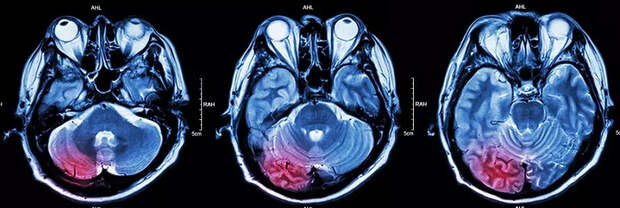

Магнитно-резонансная томография (МРТ) является высокоинформативным методом диагностики различных заболеваний. Для повышения точности исследования применяется метод контрастного усиления, при котором пациенту вводится специальное вещество – контрастное средство.

Показаниями к проведению МРТ с контрастированием являются подозрения на опухоли головного мозга, метастазы злокачественных новообразований, сосудистые патологии, воспалительные процессы внутренних органов и другие заболевания, требующие детального изучения структуры тканей и сосудов.

Процедура проводится по стандартной схеме: после предварительного обследования пациент помещается внутрь аппарата МРТ, где осуществляется сканирование исследуемой области. Введение контраста производится внутривенно перед началом или во время процедуры. Контрастные вещества содержат гадолиний, который обладает способностью накапливаться в измененных тканях, улучшая визуализацию патологических очагов.